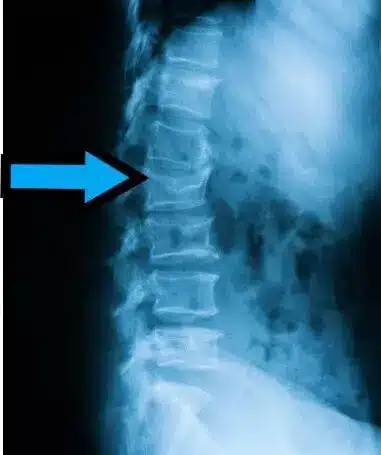

شکستگی فشاری نوعی شکستگی ناشی از فشار در استخوان مهرههای ستون فقرات است که در آن بخشی از مهره خرد شده و ارتفاع آن کاهش مییابد. این شکستگیها به سه نوع اصلی تقسیم میشوند:

- وج (Wedge fracture): در این حالت، بخش جلویی مهره در اثر فشار سقوط میکند اما بخش پشتی ثابت میماند و مهره حالتی ذوزنقهای یا شبیه گُوِه پیدا میکند. این شکستگی اغلب میتواند باعث تغییر شکل در انحنای ستون فقرات شود و گاهاً منجر به قوزپشتی (کیفوز) گردد.

شکستگی فشاری اغلب در بخشهای میانی (توراسیک) و پایینی (لومبار) ستون فقرات رخ میدهد. همانطور که گفته شد، بسته به شکل و شدت خرد شدن مهره، به سه نوع وج، کراش و برست دستهبندی میشوند:

- وج (Wedge): عموماً در بخش جلویی مهره اتفاق میافتد و شکل مهره به صورت wedge یا گُوِه درمیآید.